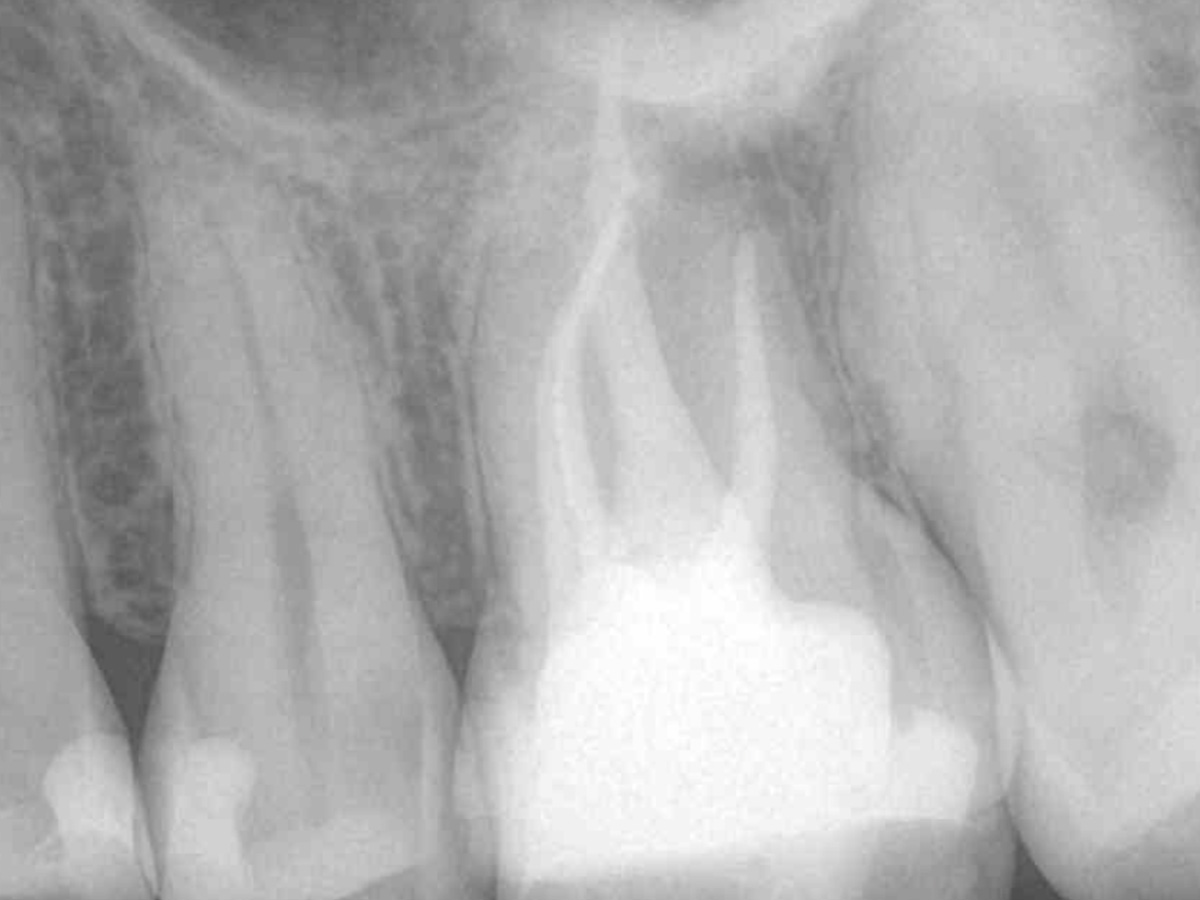

Obturation nach einer erfolgreichen Revision der insuffizienten Wurzelkanalfüllung mit einer symptomatischen apikalen Parodontitis

Der Patient stellte sich mit Aufbissschmerzen vor, wobei die klinische und röntgenologische Untersuchung eine symptomatische apikale Parodontitis an einem bereits wurzelkanalbehandelten Zahn 26 ergab. Die DVT-Aufnahme deutete auf einen unbehandelten zusätzlichen Kanal in der mesio-bukkalen Wurzel hin. Die Darstellung und Behandlung des mb2s sowie die Revision der bereits behandelten Kanäle erfolgte mit dem XP-endo® Rise Shaper bei einer hohen Umdrehungszahl von 2.500rpm.

Die Arbeitslängen der Kanäle wurden mittels elektrometrischer Messung bestimmt und die Kanäle aufbereitet. Alle Kanäle außer dem palatinalen wurden bakteriendicht mit einer Sealer-basierten Wurzelfülltechnik (Guttapercha und TotalFill® BC Sealer) verschlossen.

Für den ovalen Querschnitt der palatinalen Wurzel wurde eine warm-vertikale Technik angewendet. Dazu wurde der Guttapercha Hauptstift mit dem B&L Alpha und einem Hitzeplugger (55/.08) in der Tiefe abgetrennt und kondensiert.

Mit dem B&L Beta wurde der restliche Kanal nach der Backfill-Technik schrittweise mit erwärmter Guttapercha aufgefüllt. Die abschließenden Röntgenaufnahmen zeigen das Ergebnis, das mit den kabellosen Systemen präzise und effizient umgesetzt werden konnte.

Abbildung 4

Abbildung 5

Wurzelfüllung 26 exzentrisch

Abbildung 7

Wurzelfüllung 26 orthoadial